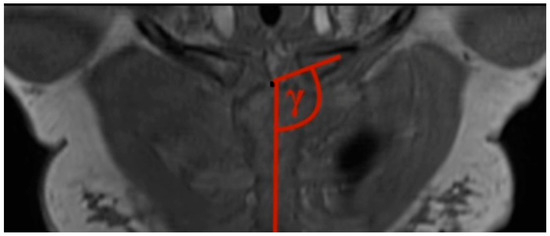

- Clavicular–sternal angle: The lengthwise axis of the clavicle is determined by a line, which is drawn from the middle of the lateral clavicle to the middle of the medial clavicle. The vertical axis of the sternum is drawn from the middle of the cranial end of the sternum to the xiphoid process of the sternum. Those two axes created the obtuse angle gamma (Figure 3).